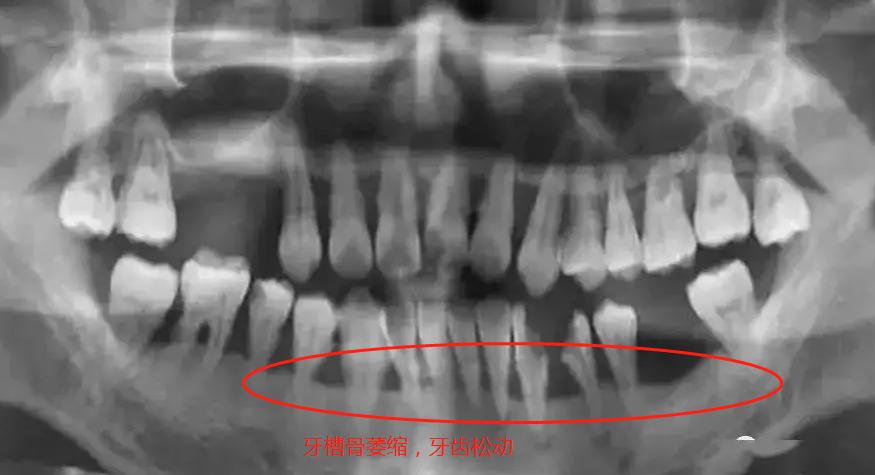

牙周炎不及时进行控制治疗,到了后期,牙槽骨吸收,牙周萎缩,牙根暴露,最终牙齿坏死,松动掉落。